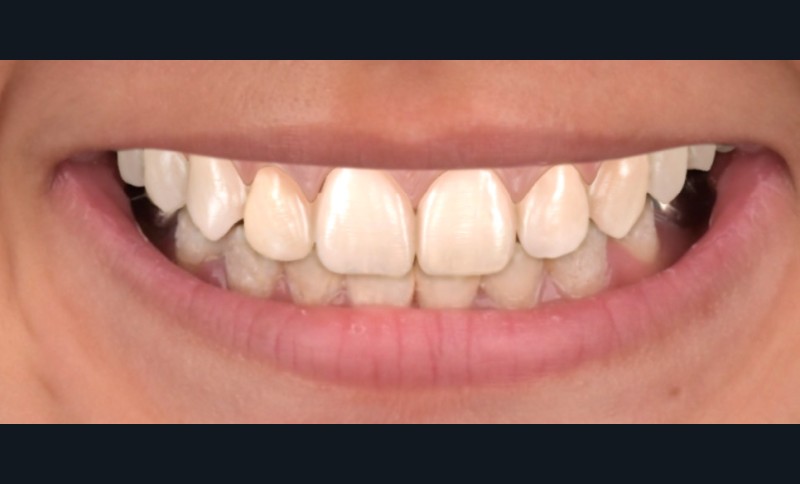

Lors de l’arrivée de la patiente, un examen clinique au fauteuil est effectué, complété par une empreinte numérique permettant l’enregistrement précis des arcades dentaires et de l’occlusion existante. Cet examen initial met en évidence une pathologie de type amélogenèse imparfaite. On note également la présence de couronnes métalliques au niveau des premières molaires, ainsi que de multiples restaurations, notamment au niveau des dernières molaires (fig. 1 à 4).

La première étape décisionnelle repose sur une analyse esthétique du visage et du sourire, réalisée à l’aide du logiciel SmileCloud. Cette analyse permet d’évaluer les proportions dentaires, la ligne du sourire et les rapports dento-labiaux. Elle confirme que le traitement vise à la fois la protection d’un émail de mauvaise qualité et l’amélioration de l’esthétique globale, avec notamment une optimisation des proportions dentaires (fig. 5 et 6).